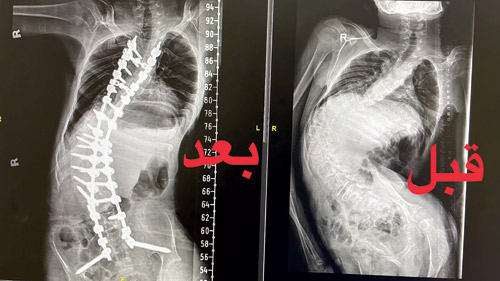

تمكّن بفضل الله فريق طبي في مدينة الملك فهد الطبية بالرياض، من تصحيح جزء كبير من الجنف «شلل دماغي» وهو ضمور في المخ من الدرجة الثالثة لمريض، ومساعدته على الجلوس مرة أخرى بعدما كان غير قادر على الجلوس بسبب الجنف الشديد الذي تعدى 140 درجة.

كما أوضح الفريق الطبي المعالج أن المريض تمكّن من المشي مرة أخرى بعد العملية بـ6 أشهر وذلك باستخدام المشاية، وقد فقد القدرة على الجلوس والمشي بسبب الزيادة في درجة الانحراف، مما أدى إلى اختلال توازنه، وعدم تمكنه من الجلوس والمشي دون مساعدة.